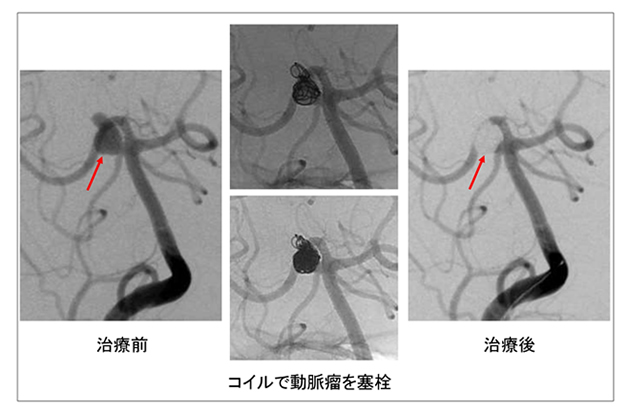

【図3】動脈瘤塞栓術の方法です。動脈瘤が最も見えやすく、特に動脈瘤が発生している血管と動脈瘤とを、きちんと分けて見られる位置に装置を合わせて治療を行います。矢印の部分が動脈瘤です。まず慎重に操作しながらマイクロカテーテル(おおむね直径0.6mm程です)を動脈瘤の中に挿入します。続いて動脈瘤の形や大きさに合わせたコイルを選択して挿入します。さらに少しずつコイルの大きさを小さくしながら、コイルの殻を強いものにしていきます。十分にコイルの殻を作ることができた後は、動脈瘤の頸部(血管との分岐部分)まで、柔らかいコイルを使ってきっちりと詰めていきます。カテーテルが押し出され、それ以上コイルを充填できない状態となったところで治療は終了です。治療後の写真では、矢印のように治療前に認められた動脈瘤は造影されない状態(動脈瘤の中に血液が入らない状態)になっています。

図3